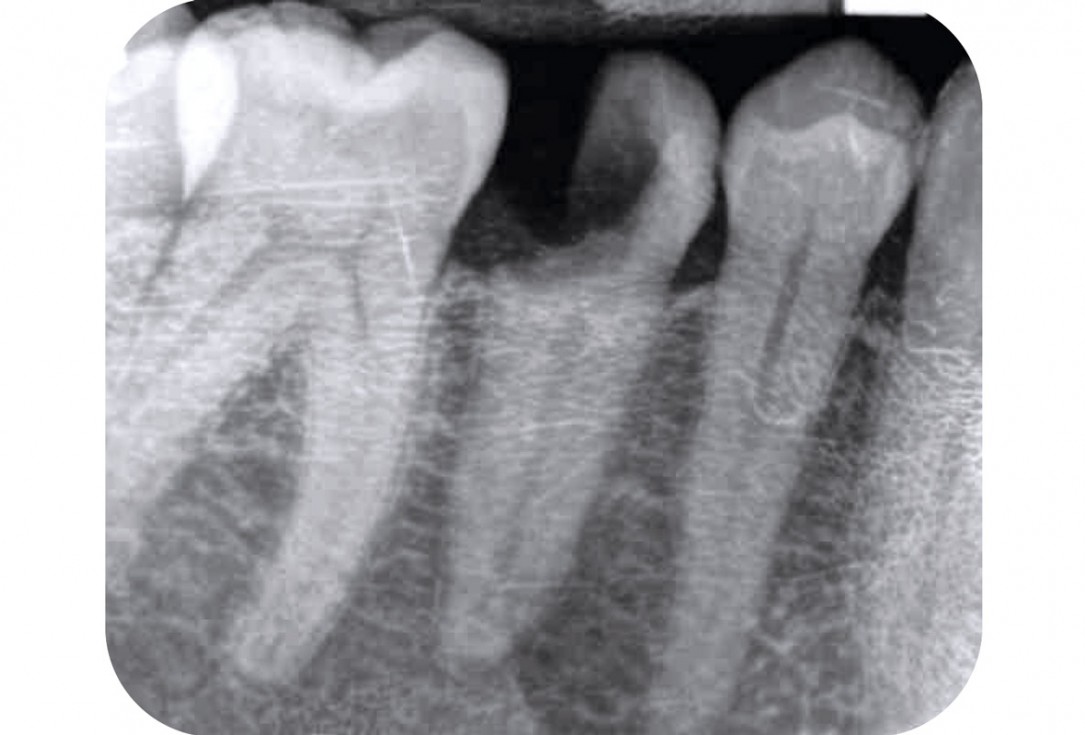

3/17 - X- ray presenting defectApplication of mucoderm® for soft tissue management around single implants at second stage surgery Dr. C. De Annuntiis

6/17 - Control X-rayApplication of mucoderm® for soft tissue management around single implants at second stage surgery Dr. C. De Annuntiis